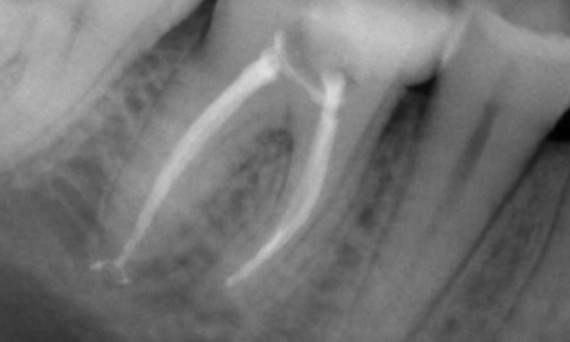

Before: Upon examination, there was a caries lesion related to the lower right first molar. Radiographic examination revealed proximity of the lesion to the pulp horn and combining it with the chief complaint, a final diagnosis of chronic irreversible pulpitis was concluded.

After: Access cavity was done as conservative as possible. TruNatomy was the system of choice due to the young patient’s age. We needed to preserve dentine as much as possible to increase the tooth ability to overcome occlusal load and increase the longevity of the final restoration.

Cairo, Egypt